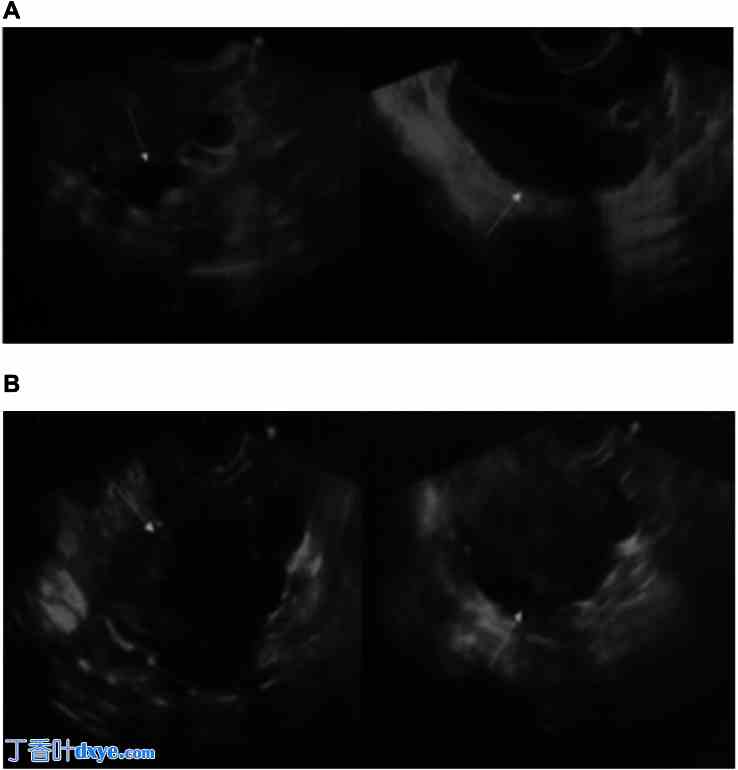

经阴道超声成像显示,道格拉斯宫腔内有一个边界清晰的圆形多囊肿块(6 厘米),内容物为均质囊性。子宫底周围有多个无回声囊性结构(图 1)。血清 CA125 水平正常。

图 1。

经阴道超声检查发现一个边界清晰的圆形多囊肿块,大小为 6 厘米,特征是位于子宫直肠的均质囊性内容物。B:在子宫底部周围观察到多个无回声囊性结构。